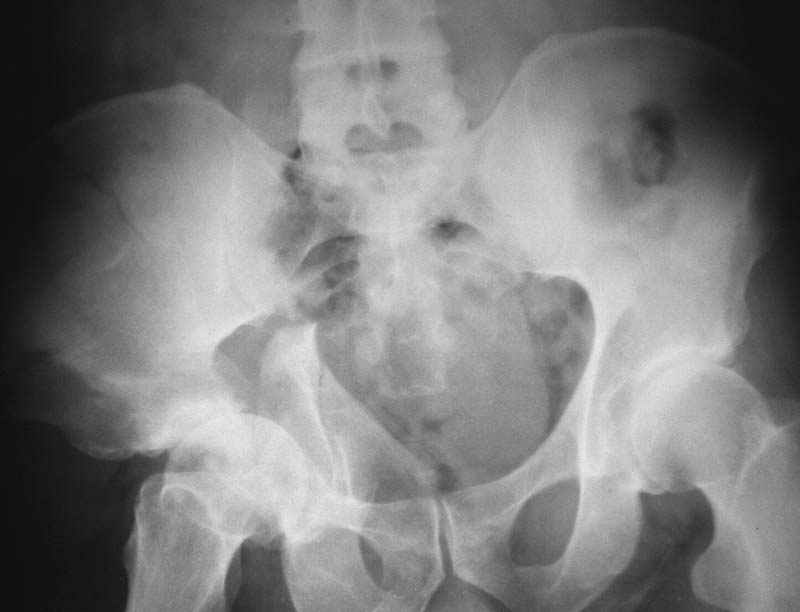

Посылаю схемы и 3D реконструкцию подобного повреждения. Называется он полным высоким двухколонным переломом вертлужной впадины, а "переломы крыла и тела подвздошной кости" входят в это понятие.

Вариантов остеосинтеза много (можно и не оперировть, т.к. конгруентность при таких переломах как правило сохраняется)

1 закрытая репозиция аппаратом + фиксация через проколы винтами

2 закрытая репозиция передней колонны + открытая задней колонны из задне-неружного доступа

3 открытая репозиция передней колонны из подвздошнго доступа + открытая задней колонны из задне-наружного доступа

4 открытая репозиция из илиоингвинального доступа

5 открытая репозиция из Y образного доступа

Я бы ориентировался на Y образный доступ

или из двух если есть сомнения в целостности задних отделов крыла.

прикладываю схему доступа и случай.

Одним задне наружным переднюю колонну не достать, а илио-ингвинальный более сложный не позволяет контролировать суставную поверхность и трудно управлять задней колонной.